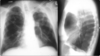

80

What does this CXR show?

* Right mainstem intubation

81

Is this a proper placement of a central line?

* No, the tip (smaller red arrow) is within the right ventricle. Pt will probably experience PVCs. * The catheter tip should lie between the most proximal venous valves of the subclavian or jugular veins and the right atrium.